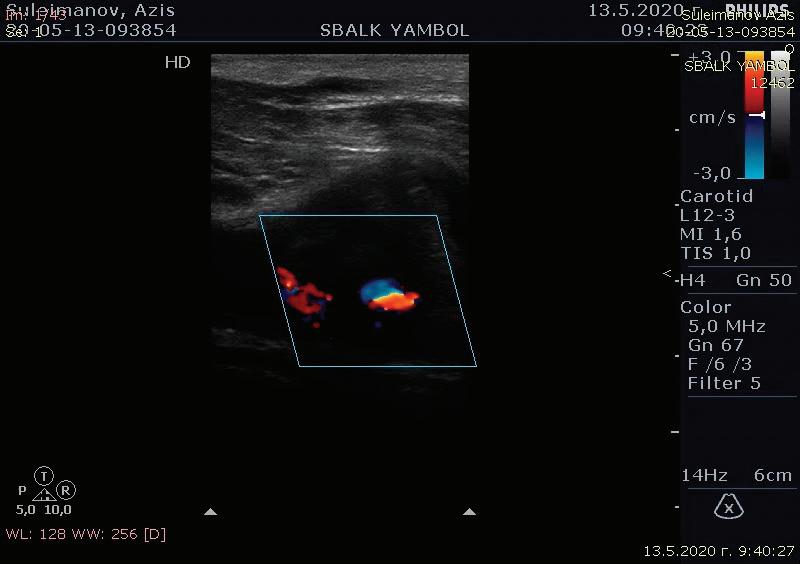

60 КЪСНА РЕВАСКУЛАРИЗАЦИЯ СЛЕД ОСТРА ТРОМБОЗА НА А. СУБКЛАВИА СИНИСТРА –КЛИНИЧЕН СЛУЧАЙ Р. Рунков

62 РЕТРОГРАДНА ПЕРКУТАННА